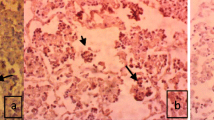

Nigerian strain of Peste des Petit Ruminant (PPR) virus and Mannheimia haemolytica (MH) biotype A serotype 2, was used successfully to reproduce a concurrent disease in West African Dwarf goats. The development of the various pathological features were studied at regular intervals following infection. The acute inflammatory reaction which had developed by day 3 after initial infection was characterised by flooding of the alveoli by neutrophils, oedema, hemorrhage and syncytial cells together with a moderate bronchial and bronchiolar epithelial necrosis. This progressed to a milder acute broncho interstitial pneumonia with giant cells. At this stage, the mucosal immunity were well developed especially the aggregate form of NALT and more of nodular forms of BALT. The organisms were demonstrated with strong immunostaining in the necrotic center, necrotic alveolar wall, fibrin, serous exudate, and degenerated leukocyte in the alveoli and respiratory airways. The bacterial antigens were observed as a strong immunostaining in the blood vessels of the nasal septum, sinusoid in the liver and interstium of the kidney, cytoplasm of alveolar macrophages, pneumocytes, bronchial and bronchiolar epithelium, in the monocytes in the blood vessels. These findings confirmed the enhancement of MH tropism especially in the respiratory tract, liver and kidney. It also showed that West african dwarf goats are highly susceptible to the intratracheal combined infection of PPR virus and MH. The fact that the infection induces strong mucosal responses, this phenomenon can be explored in Africa with the use of combined PPR virus and MH intranasal vaccines to curtail the menace of pneumonia associated with the combined infection on field.